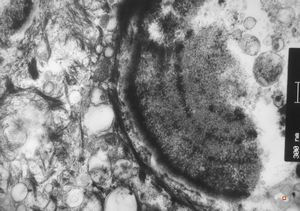

F,23y. | normal oral mucosal epithelium

F,23y. | normal oral mucosal epithelium - hemidesmosomes and anchoring fibrils